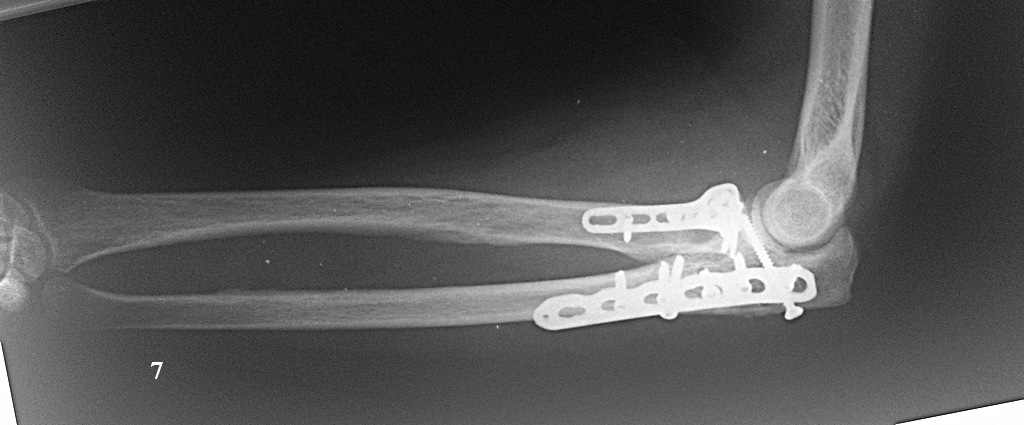

Хочу попросить совета у сообщества по поводу следующего клинического случая. Женщина, 65 лет. Закрытый перелом Монтеджи слева в октябре 2013 года. (рис. 1, 2). Для наглядности сделал скиаграмму перелома (рис. 3, 4). На 8-е сутки накостный остеосинтез пластинами с угловой стабильностью. Головка луча была восстановлена из отломков (рис. 5) и собрана на спицах одну из которых скусили и оставили под пластиной.(рис. 6). Вроде получилось стабильно, видео на операции по этой ссылке:

http://youtu.be/vdeYGTWrTmkНа рентгенограмме тоже вроде ничего. (рис. 7, 8).Из реабилитации порекомендовали заниматься с первого дня движениями в суставе (пронация/супинация, сгибание/разгибание), выполнять несложную домашнюю работу. Видео объма движения на 7-е сутки после операции по ссылке: http://youtu.be/KyPAUmEIhs4